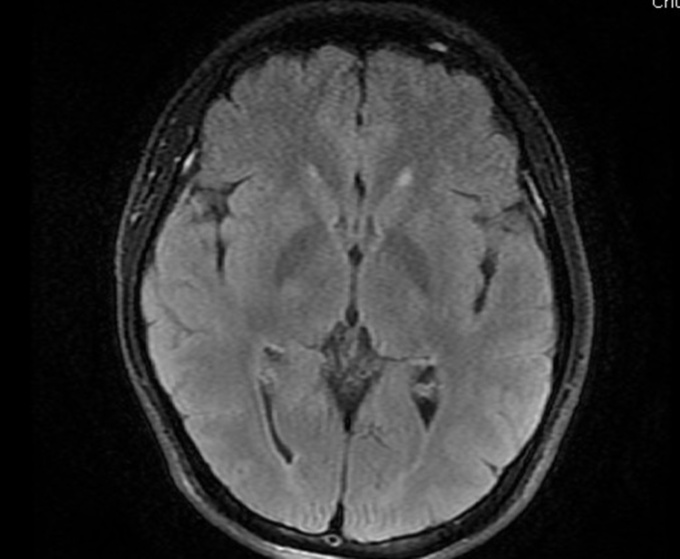

Người đàn ông 32 tuổi, mất thị lực đột ngột rồi nhanh chóng bình thường trở lại, vài ngày sau thì đột quỵ não.

Các bác sĩ Bệnh viện Bãi Cháy ngày 19/1 thông tin anh đang đi trên đường thì có biểu hiện hoa mắt, chóng mặt, liệt hoàn toàn nửa người phải, không nói được, được đưa vào viện cấp cứu.

Bác sĩ chẩn đoán bệnh nhân bị nhồi máu não cấp giờ đầu (mất thị lực là dấu hiệu sớm), khởi động quy trình điều trị đột quỵ não cấp, dùng thuốc tiêu sợi huyết đường tĩnh mạch. Sau tiêm thuốc 30 phút, cơ lực của bệnh nhân cải thiện, tỉnh táo trở lại, nửa người bên phải dần cử động được. Bệnh nhân dần phục hồi, nói chuyện, đi lại được.